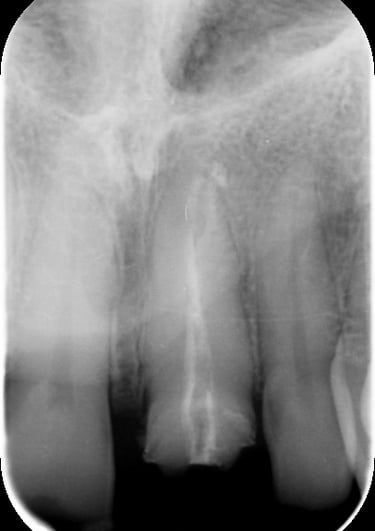

Trattamento Canalare Incongruo

Trattamento Canalare Congruo

Trattamento endodontico inadeguato: il precedente trattamento canalare era insufficiente, lasciando il dente vulnerabile a infezioni e compromettendone la prognosi a lungo termine.

Il primo step è stato il ritrattamento endodontico, essenziale per garantire la salute a lungo termine del dente. Dopo la rimozione della vecchia otturazione canalare, è stata effettuata una detersione accurata con irriganti specifici e successiva otturazione tridimensionale per prevenire recidive infettive.